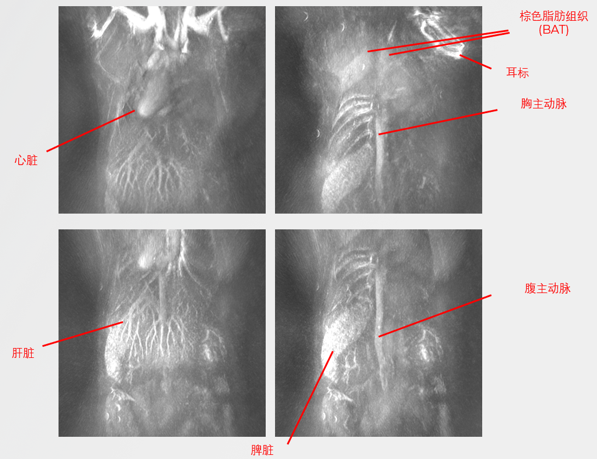

TriTom 小動物光聲成像系統(tǒng)利用光聲斷層掃描成像技術(shù)對小動物成像,獲取真實(shí)的高空間分辨率3D圖像,成像對象包括:小鼠、離體組織、熒光探針樣品等。

美國Photosound公司生產(chǎn)的小動物光聲斷層掃描成像系統(tǒng)是一款無創(chuàng)三維成像平臺。利用光聲斷層掃描成像技術(shù)對小動物成像,獲取真實(shí)的高空間分辨率3D圖像,成像對象包括:小鼠、體重小于200g的大鼠、離體組織、熒光探針樣品等。單次掃描最快僅需36秒即可獲取深層組織的3D圖像,實(shí)現(xiàn)真正的三維光聲成像??稍谌我馇忻娣治鰣D像,包括橫向解剖平面、矢狀和冠狀解剖平面以及不規(guī)則的解剖平面。橫向解剖平面的空間分辨率150*150μm,矢狀和冠狀解剖平面分辨率150*230μm。分子成像靈敏度100 nM ICG。

光聲成像結(jié)合了光學(xué)成像的高對比度和超聲成像的深度穿透能力。小動物麻醉后浸入去離子水中,口鼻始終處于麻醉氣體管路中維持麻醉狀態(tài),脈沖激光器生成特定波長的激光照射實(shí)驗(yàn)動物,動物體內(nèi)特定的生物分子(如血紅蛋白、黑色素、水、脂肪或外源性分子探針)吸收光能后被激發(fā)并轉(zhuǎn)化為熱能,導(dǎo)致局部溫度升高和熱彈性膨脹產(chǎn)生超聲波,使用超聲換能器檢測超聲波并轉(zhuǎn)換為電信號,通過圖像重建算法生成高分辨率的光聲圖像。

除3D解剖結(jié)構(gòu)圖譜外,TriTom小動物光聲成像系統(tǒng)還可以對體內(nèi)生理參數(shù)進(jìn)行空間解析評估,例如體積血含量和氧合情況,無需注射造影劑。